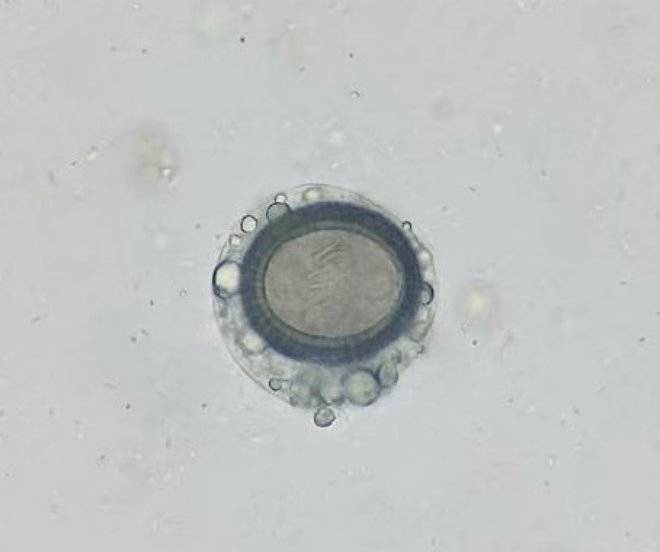

53号 S53 带绦虫卵

最外层是一层无色薄而透明的卵壳(见图1-2),较脆弱,自孕节散出后多数已脱落,脱掉卵壳的带绦虫卵呈球形或近似球形(见图3),卵壳内有一圈较厚、棕黄色的呈放射状条纹的胚膜,卵壳与胚膜间有明显的空隙,其间有颗粒。胚膜内是球形的六钩蚴,有3对小钩,这里隐约可见3-4个小钩。

96号 S96 绦虫卵的奇幻变身记

这颗自带"蝴蝶翅膀"造型的虫卵,堪称寄生虫界的"艺术大师"!30-40微米的卵壳被自然雕琢成对称的蝶翼状,薄如蝉翼却坚不可摧。透过晶莹的"翅膀",能看到六钩蚴正挥舞着小钩子彩排"破茧秀",周围的卵黄颗粒像撒了一地星星糖。温馨提示:若在显微镜下邂逅这枚"生物珠宝",请勿沉迷它的颜值—